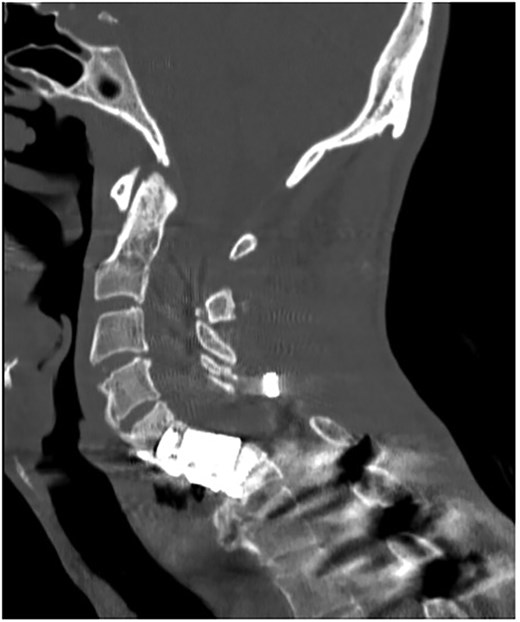

A 35-year-old male presented with a month-long history of dysphagia, severe headache, and posterior neck pain that radiated to the occiput. His medical history was significant for cervical surgeries, including an anterior cervical discectomy and fusion (ACDF) at C5/C6 one year and two months ago (Fig. 1). Shortly thereafter, the patient underwent revision surgery along with posterior plating from C5 to T1 due to osteomyelitis, worsening cervical deformity, and retropharyngeal abscess (Fig. 2). Initial workup included a noncontract computed tomography (CT), demonstrating increased gas density at C6 corpectomy site and post cricoid region (Fig. 3). A swallow study was obtained based on suspicion of a perforation and demonstrated extraluminal leakage of contrast posteriorly at the C6 level, consistent with initial CT (Fig. 4). Surgery included removal of the anterior and posterior hardware and esophageal repair. Although initially the esophageal injury was suspected to be related to the hardware, intraoperatively, it was found the instrumentation was not in communication with the esophagus. This confirmed the perforation was unrelated to direct injury from the cervical hardware construct, which was intact. The esophagus was repaired with a pectoralis flap. The postoperative course was uneventful, and the patient was discharged home after one week. The patient later died due to severe complications of substance abuse unrelated to the operation.

Sagittal T2-weighted MR of prior retropharyngeal abscess that led to revision and posterior plating from C5 to T1.